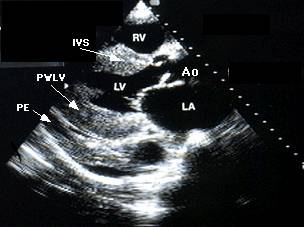

Ecocardiografia permite evaluarea afectarii functiei contractile, excluderea unor boli valvulare sau pericardice. Se apreciaza forma si functia VS (tipic VS globulos cu functie contractila global alterata), gradul insuficientelor valvulare, prezenta trombozei intracavitare (intraatriala sau intraventriculara). Cresterea dimensiunilor cavitatilor stangi si drepte este progresiva cu cresterea clasei functionale NYHA. Producerea emboliilor se asociaza cu dimensiunea VS si fractia de ejectie (FE).

-Ecocardiografia demonstreaza un grad de disfunctie VS - adesea regionala, sau kinetica poate fi normala. Se pot intalni pereti ingrosati, trombi VS, functie diastolica (umplere diastolica) anormala.